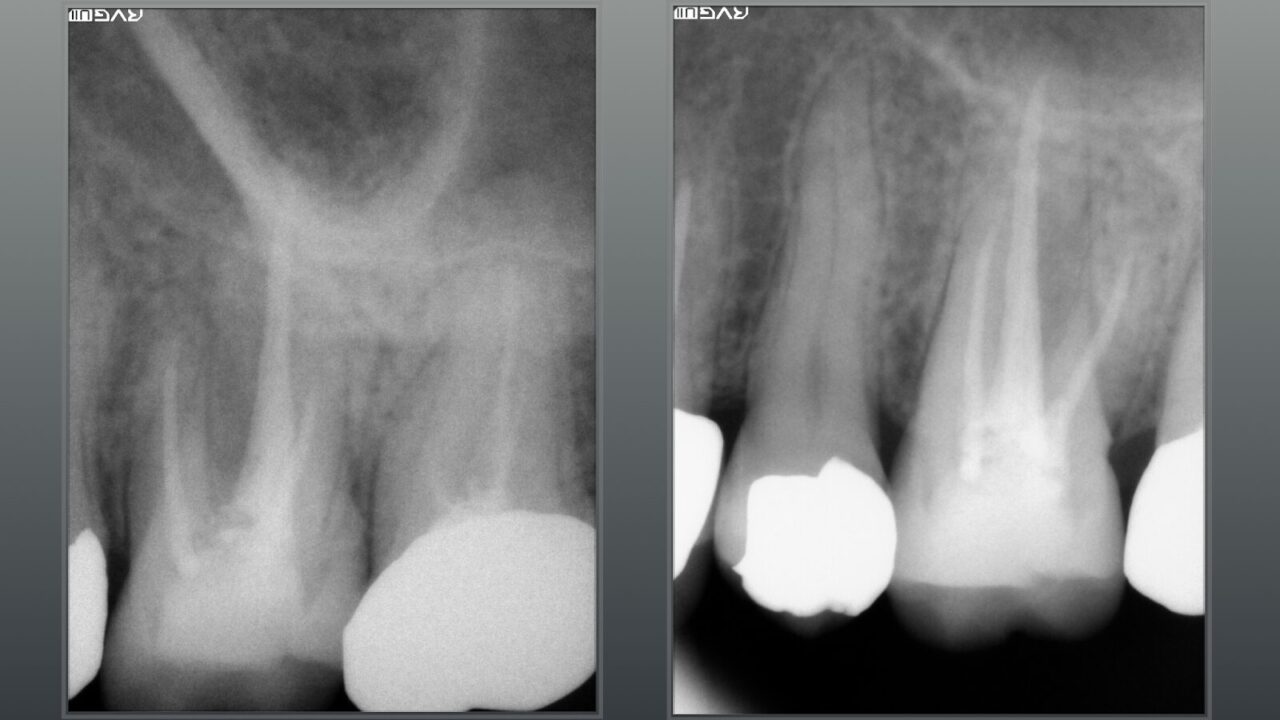

術前のレントゲン写真、歯根を取り巻く骨吸収像が確認できます。

術後のレントゲン写真、術前のレントゲン写真と比べると骨吸収像が改善され骨の再生が確認できます。